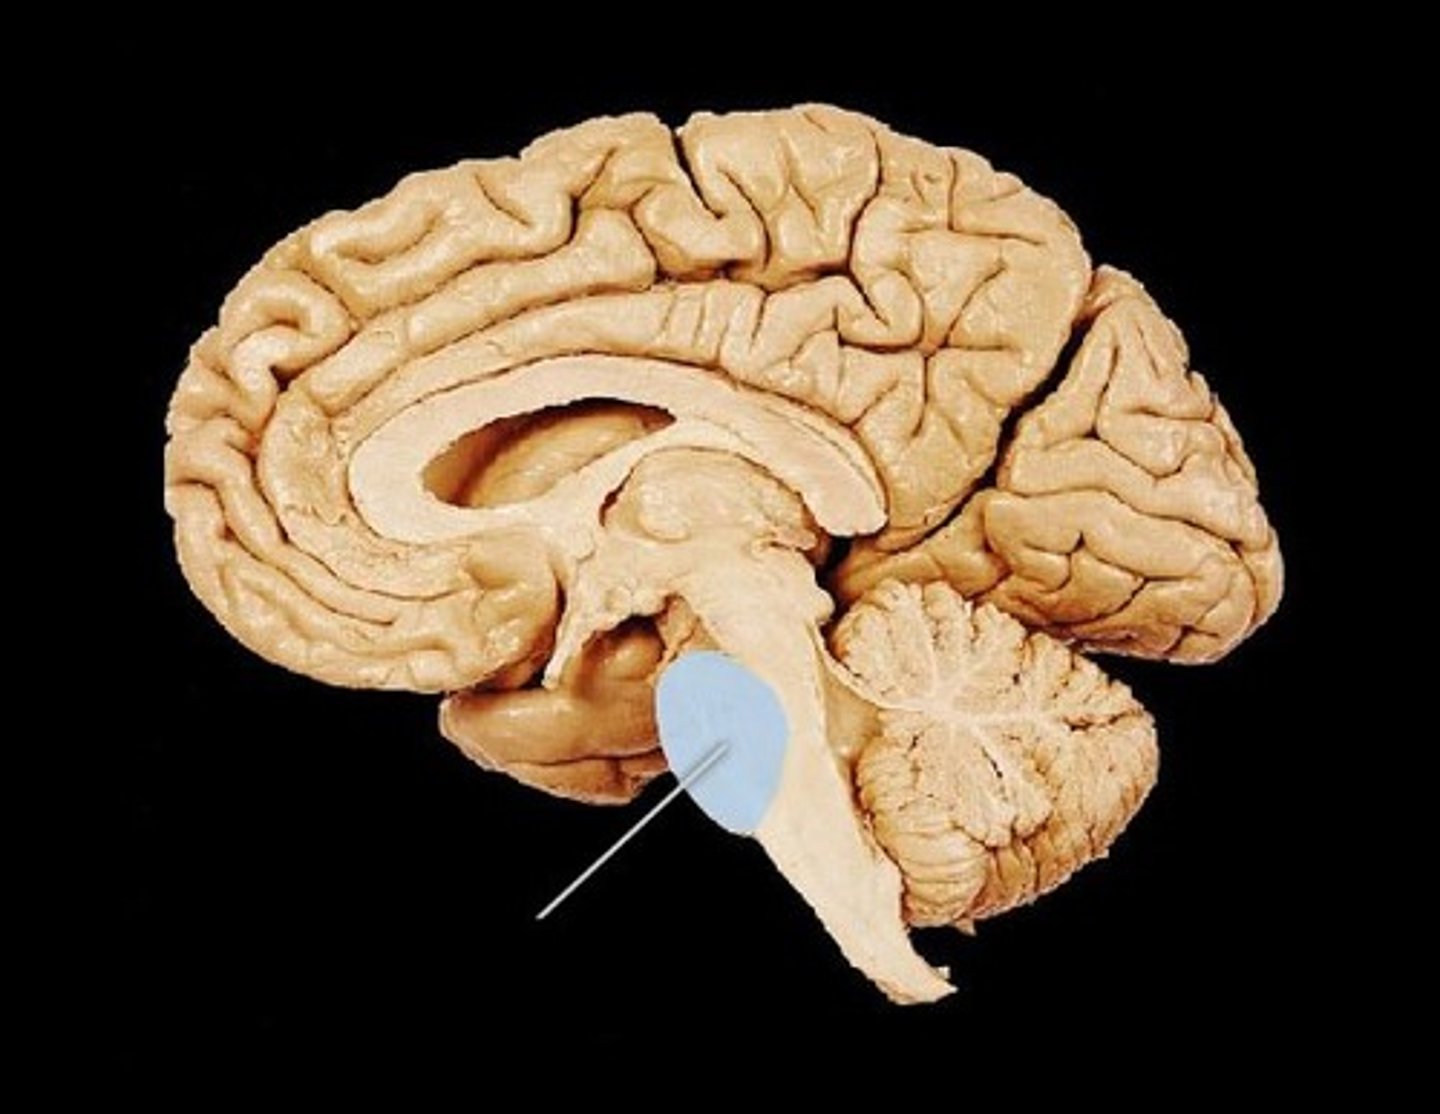

Medula

Part of the brain stem which regulates respiratory and cardiovascular systems